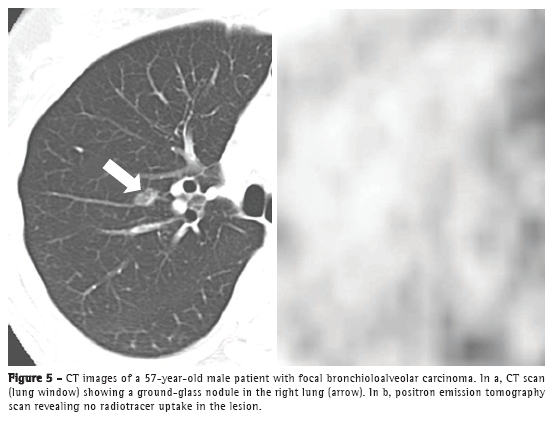

Positron emission tomography (PET) is considered a fundamental tool in the staging, treatment, and follow-up of lung neoplasms (Figure 4).

However, it is of note that pure BAC might not show increased 18F-fluorodeoxyglucose (FDG) uptake,(6) given that these tumors are usually indolent, slow growing, and well differentiated. Therefore, the lack of FDG uptake does not exclude the possibility of neoplasms, such as BAC, small lesions, and indolent cancers. Martins et al.(17) studied the diagnostic accuracy of PET in the assessment of solitary pulmonary nodules and obtained, among the 32 patients studied, only one false-negative result, a case in which the final diagnosis was BAC. Therefore, CT analysis is mandatory for the diagnosis (Figure 5).